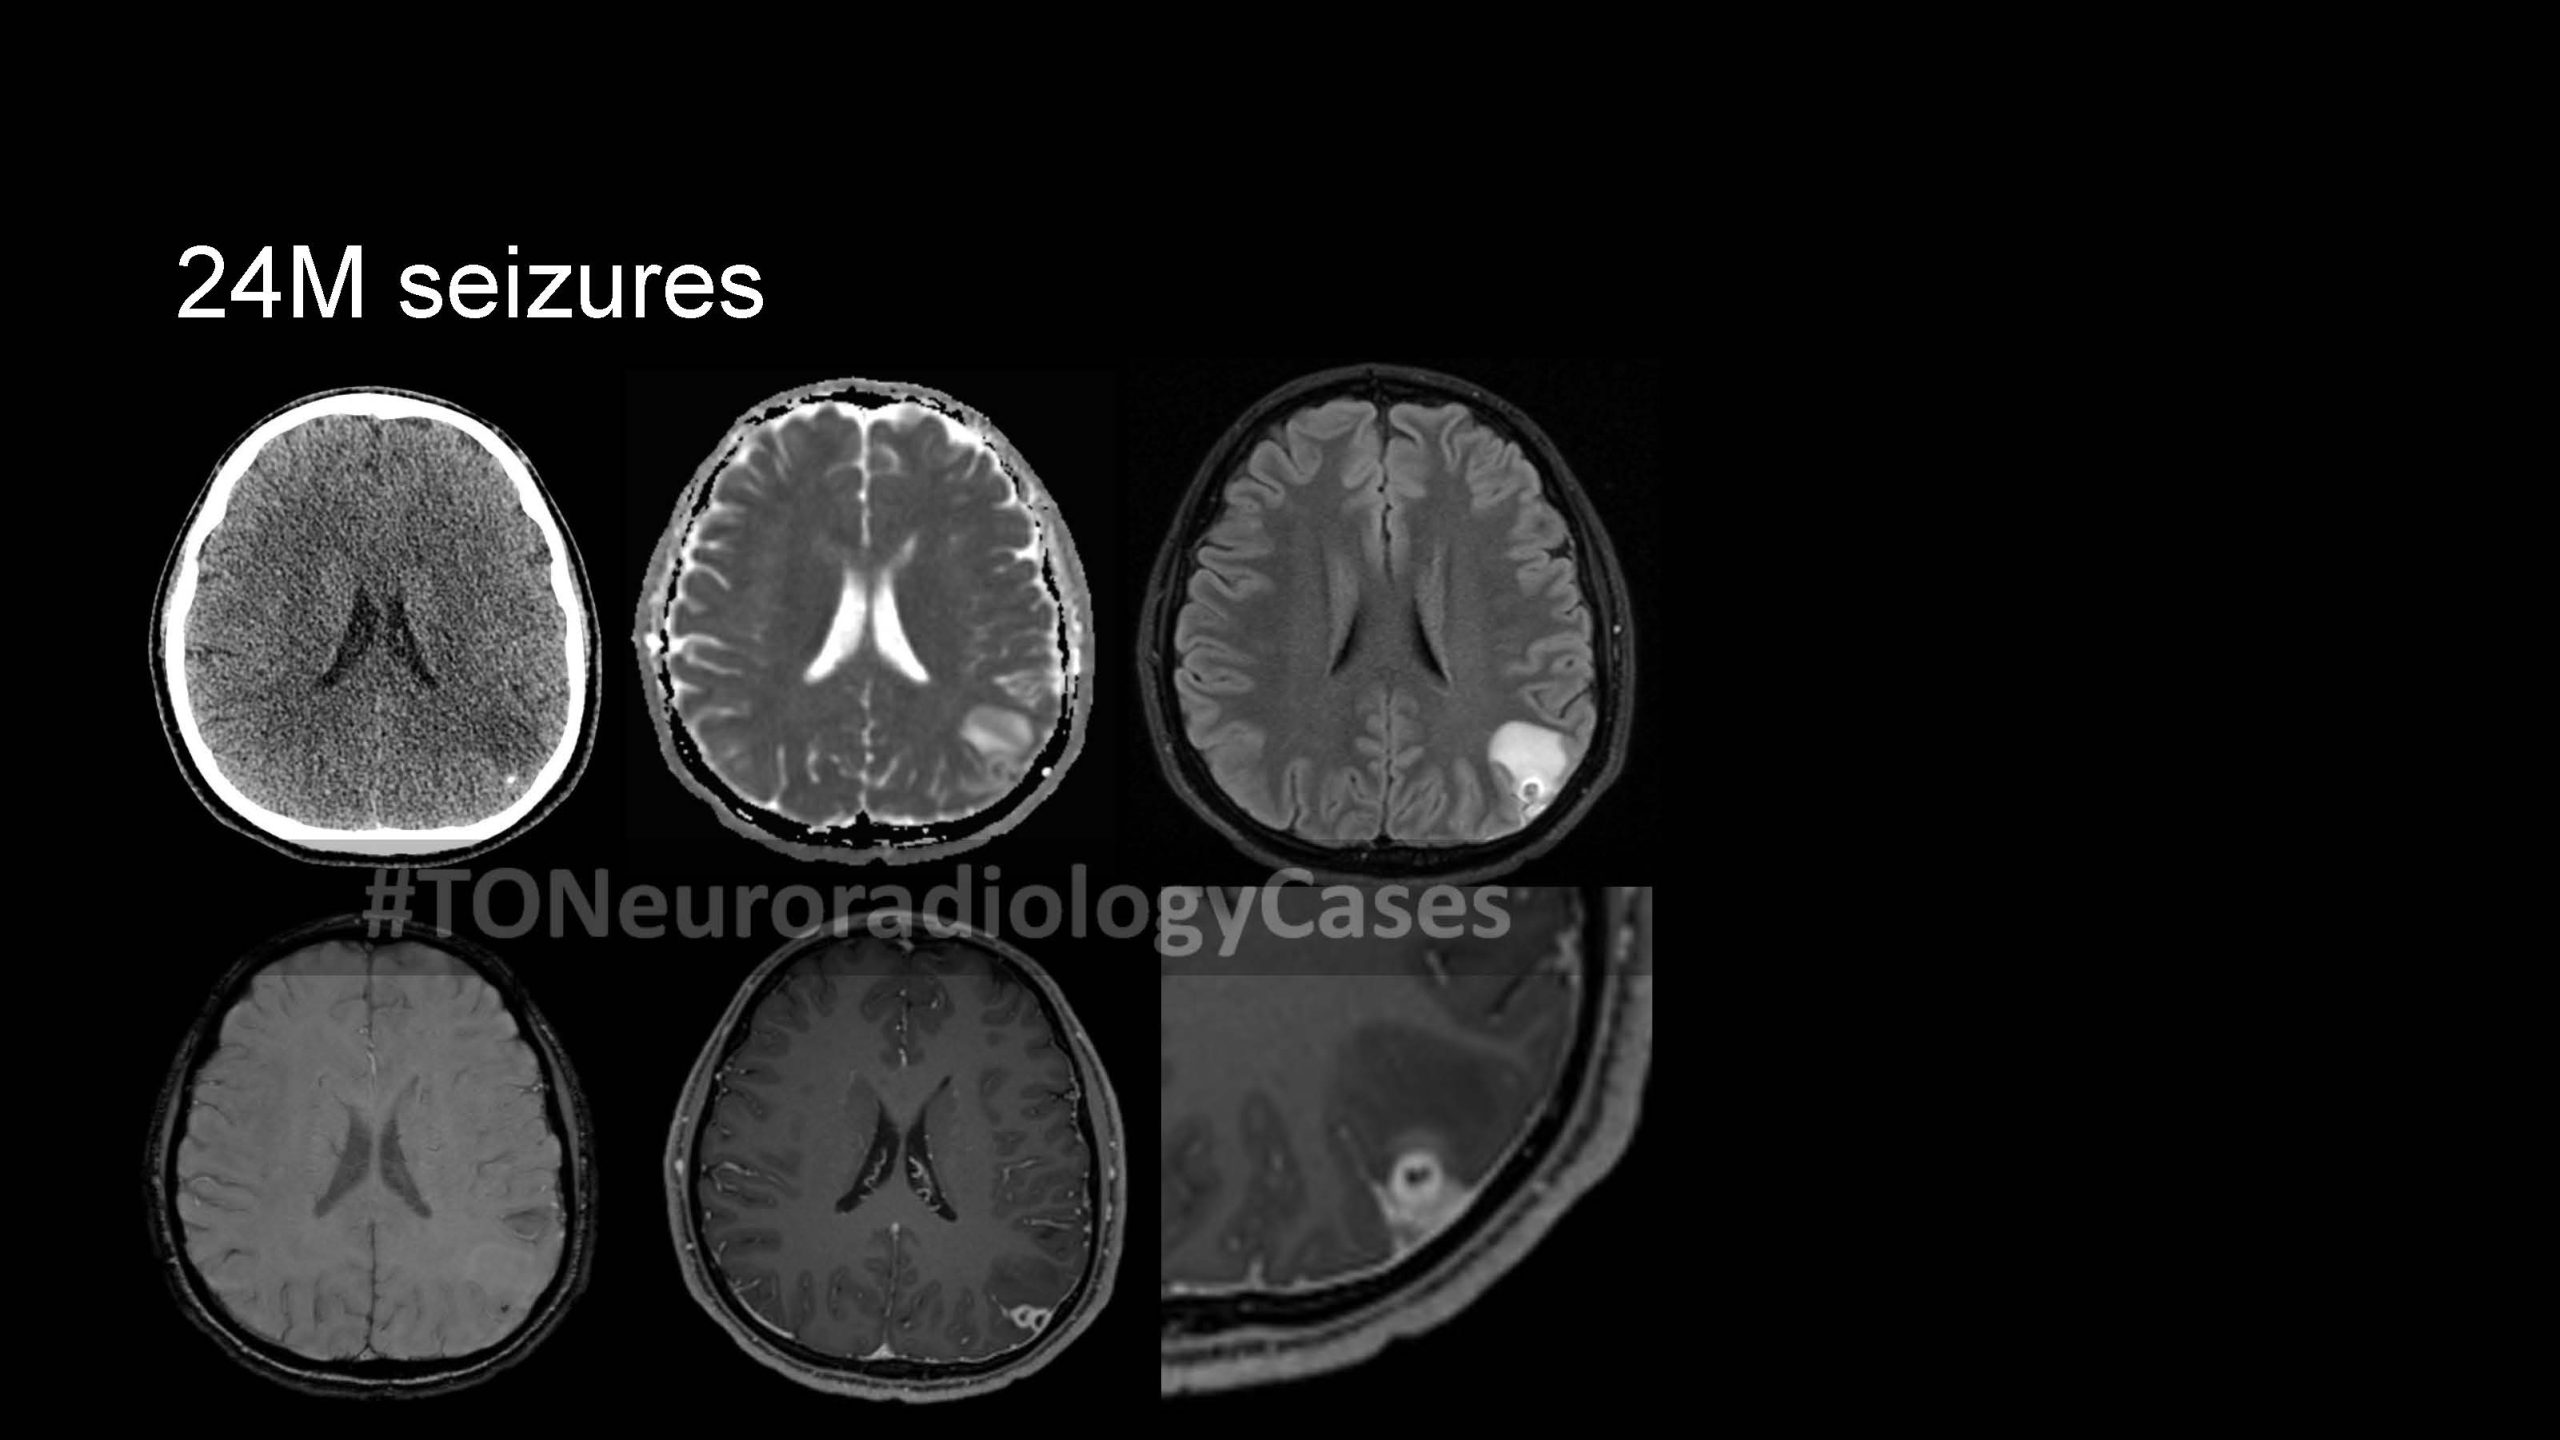

DR. AMY CHEN’S

Neuroradiology Case of the Week

@ Toronto Radiology

Over the past few years, I’ve had the pleasure of curating a “Case of the Week” contest with contributions from radiologists across the city, designed to challenge and engage our neuroradiology fellows at the University of Toronto. This collection showcases a range of neuroradiology cases from our city and have been a fun part of our fellow’s educational experience. I am excited to share this resource with a wider audience, now featured on our Toronto Radiology departmental website.